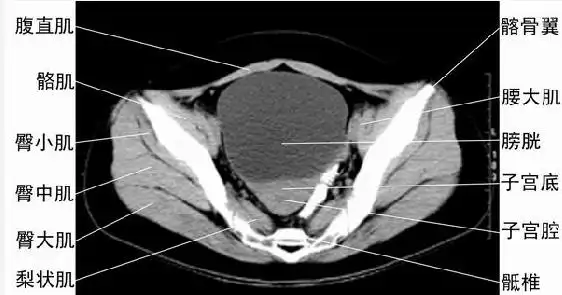

盆腔ct诊断课件